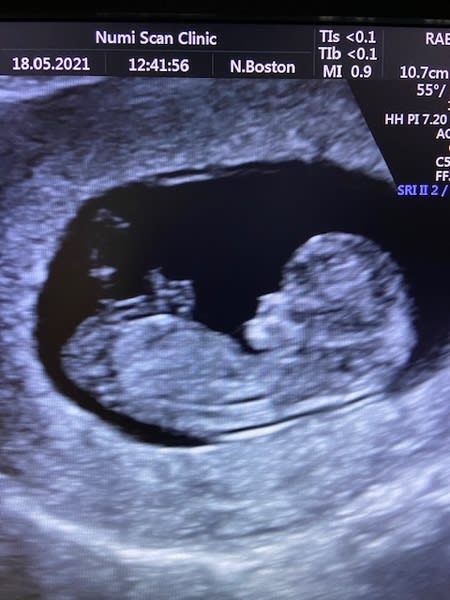

An early scan may show whether or not you have a viable ongoing pregnancy. The scan will let you know if there is a heartbeat, which would be visualised not heard at this stage and beats per minute taken using a M-mode which is a safe way to measure your baby's heart rate in early pregnancy. The scan will also check how many babies you are carrying and measure the baby to give you an accurate gestational age. It's important to be aware that dates can sometimes be a little off due to the variability in cycle lengths i.e. when ovulation took place. If the dates don't match the exact number of weeks since your last period then it could be down to cycle length. These signs are all quite positive but if there are any signs such as bleeding or all that needs to be seen cannot not be confirmed, you may need a further scan in a week or two to check what’s happening.

The best time to have a scan is from 7 weeks. At this time it would normally be possible to see a heartbeat but sometimes dates may be a little off and a second scan may be necessary.